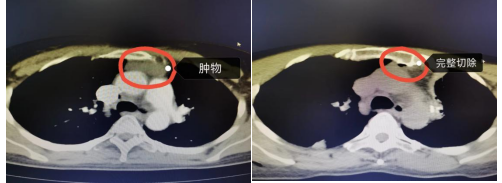

近日,55岁的夏女士在外院体检时发现纵膈内有一处大小超3cm的肿物,于是便来到涪陵区人民医院心胸外科门诊就诊。彭剑冬医生初步诊断为纵膈肿物,但是具体性质不能明确。患者及家属均希望手术切除并送检明确肿物性质。经医生仔细询问患者病史,患者糖尿病严重,一直通过口服降糖药控制血糖效果不好,于是便收住入院监测并调整血糖指标。住院开始测得患者血糖均是17-18mmol/L,住院后联合内分泌科一起调控,患者血糖基本趋于正常,具备手术条件。综合评定后,彭剑冬建议患者进行“单操作孔胸腔镜手术”。

在内分泌科、麻醉科的协助下,最终手术顺利完成。患者术后第二天已经下地活动,预计近期便能康复出院。

单操作孔胸 腔镜手术,是目前最为实用的胸外科微创技术手段。仅需要在胸壁开放一个3cm左右的切口作为手术操作通路,以及一个1cm左右的切口作为观察孔及术后留置引流管,便能完成复杂的胸科手术。对比开胸手术的“粗暴”,其优点是微创,美观,术后疼痛感减轻,康复时间更快,术后患者情感及功能状态更好。